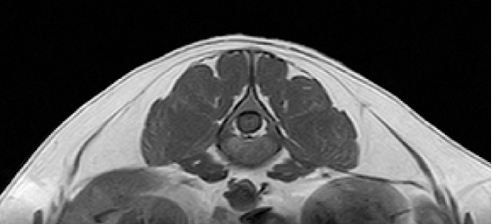

【画像診断】~ダックスフンド、雄10歳、グレート3の椎間板ヘルニア~

▲犬のほぼ正常な椎間板のMRI像(キャミックに依頼)